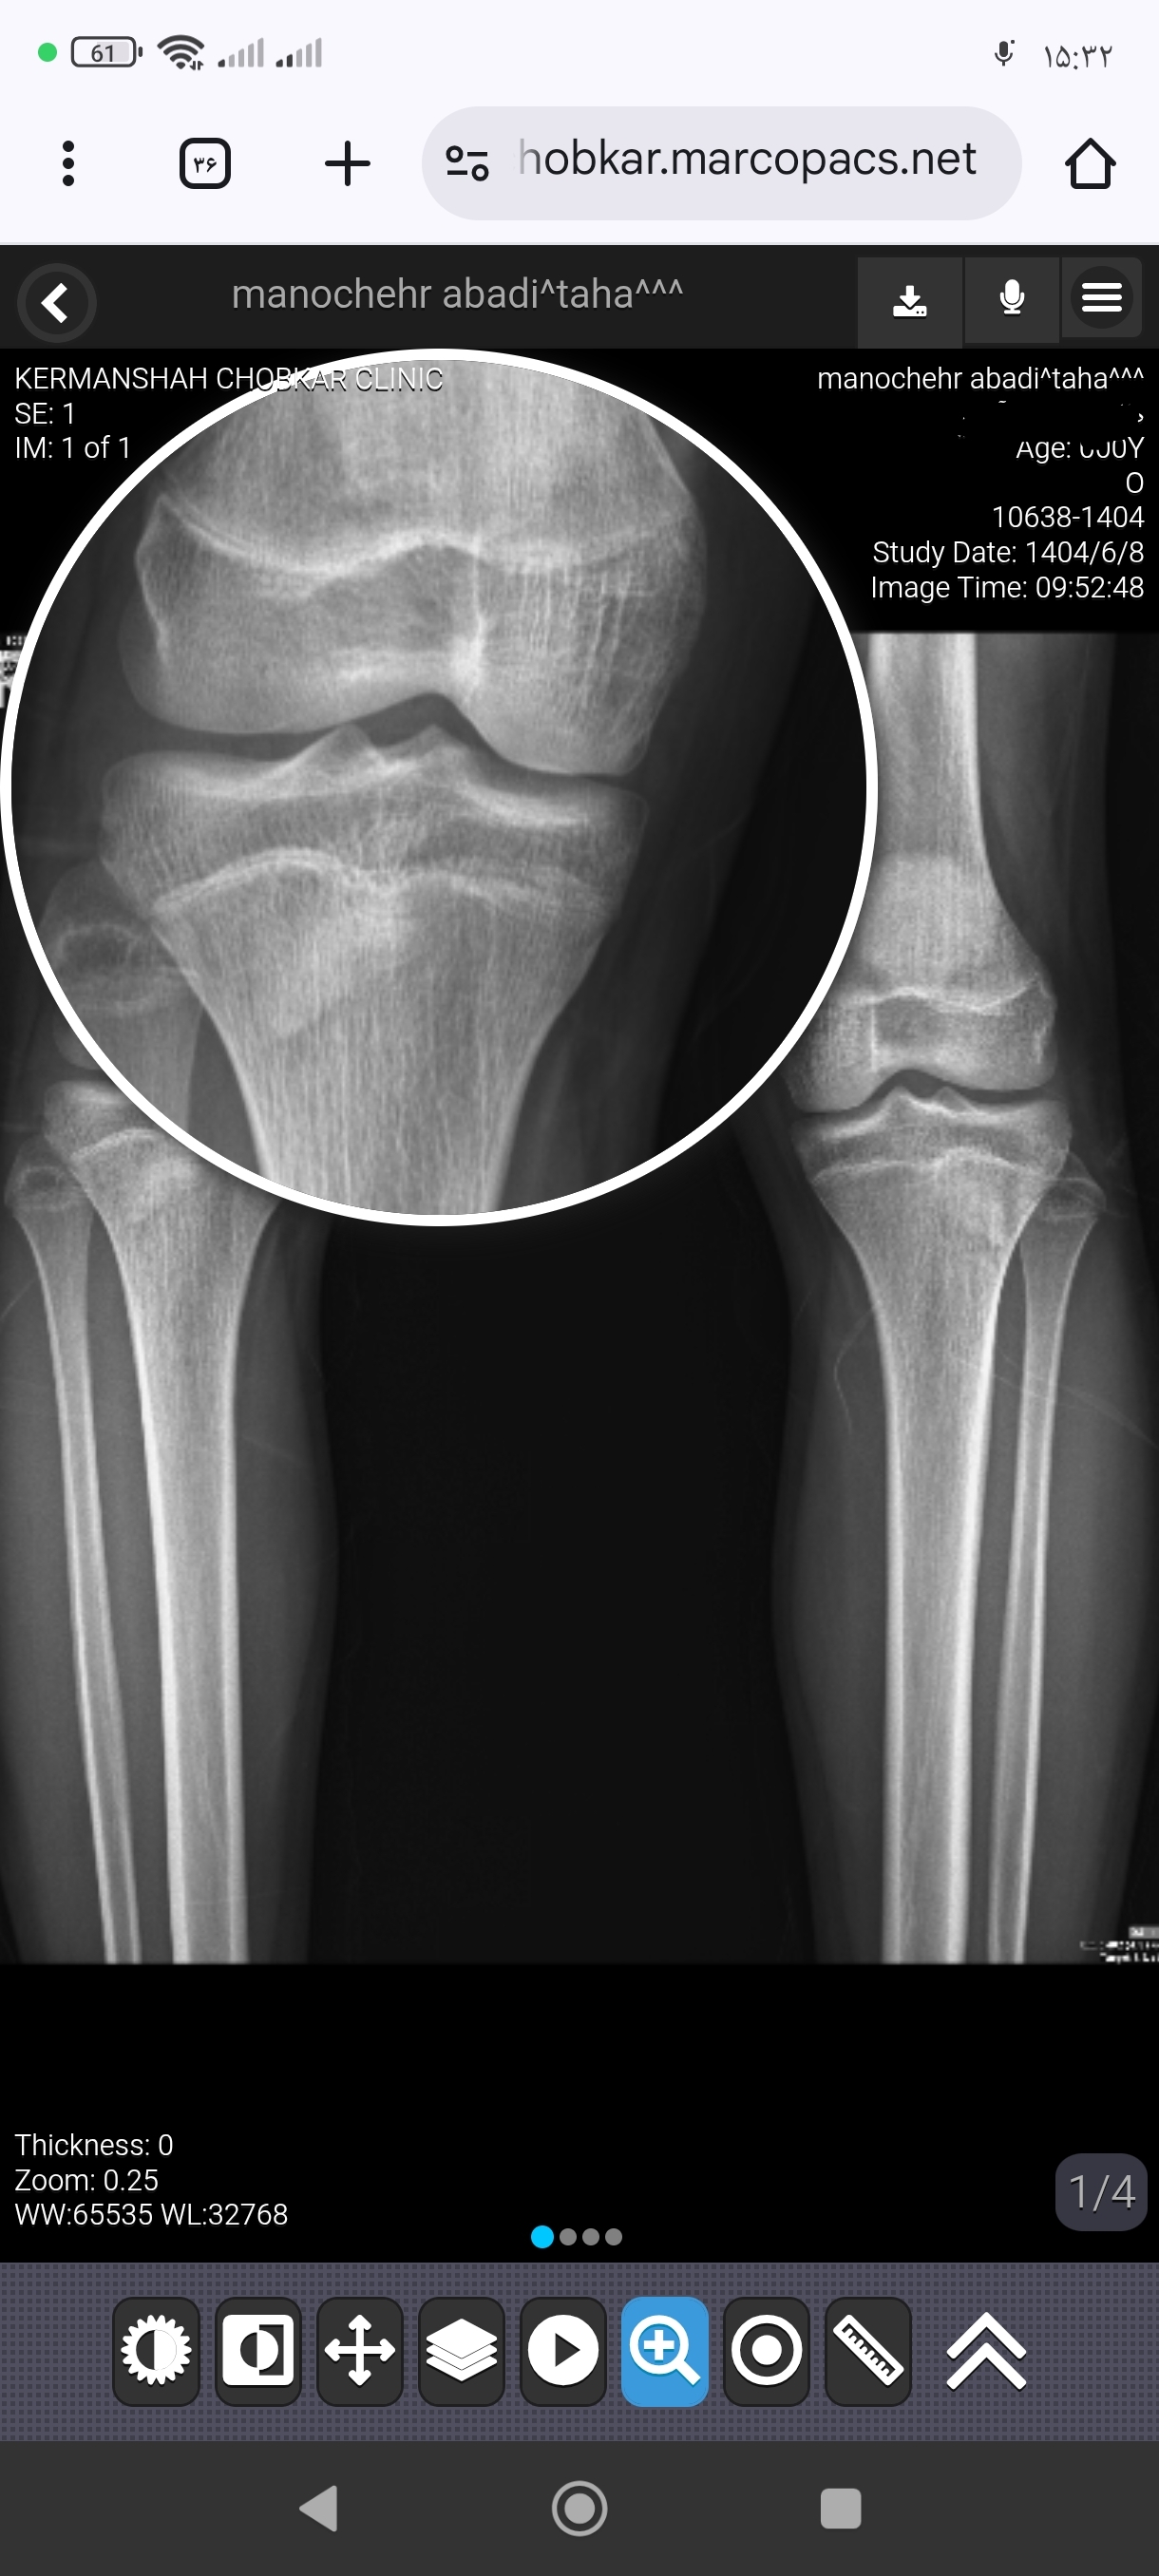

رضا سن : 18 وزن : 62 قد : 175

سلام درود بر شما در این عکس صفحات رشد بازه یا نه یا چقد دیگه امکان رشد وجود داره ممنون از شما و این عکس یک هفته پیش گرفتم